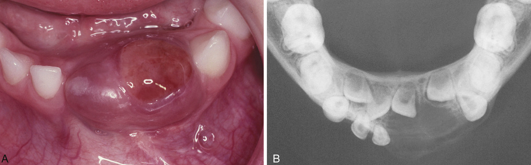

central giant cell granuloma